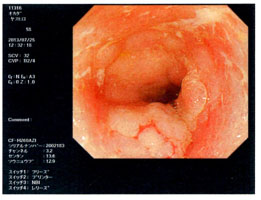

| 内視鏡検査(胃カメラ) |

切り取った癌細胞 |

| 内視鏡検査(大腸カメラ) |

がん予備群ポリープ |